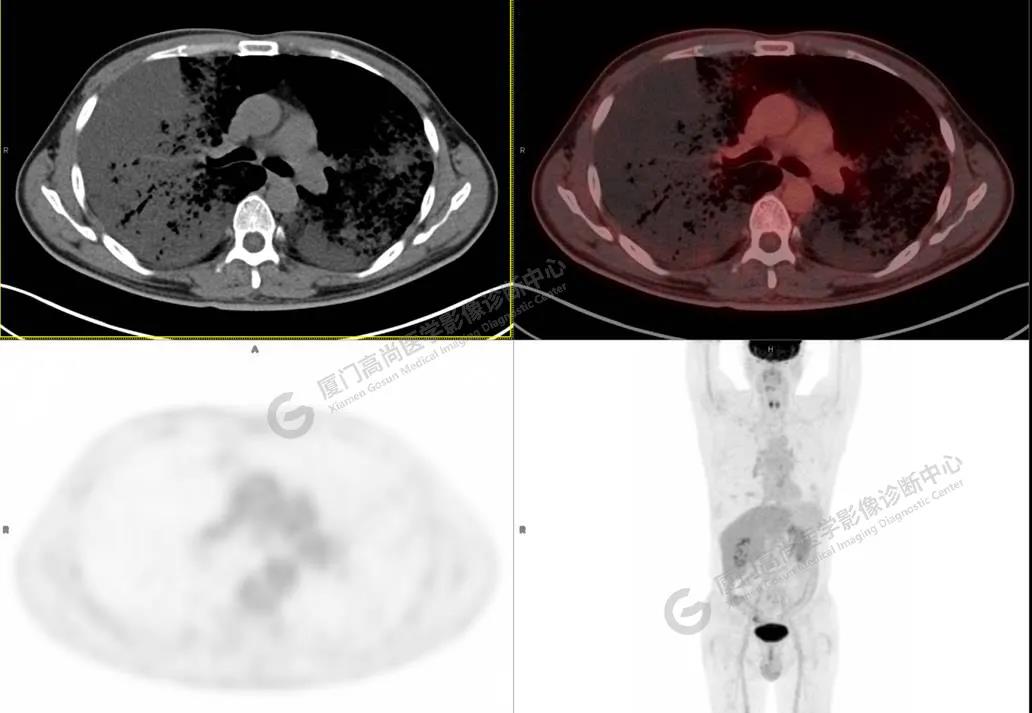

PET/CT影像圖

圖1

PET/CT所見:雙肺大片實(shí)變影及磨玻璃影,部分呈地圖樣改變,累及右肺尖,部分放射性攝取輕微增高,SUVmax 1.77,其內(nèi)見多發(fā)支氣管充氣征象。

影像診斷: 雙肺大片實(shí)變影及磨玻璃影,大部分代謝不高,局部代謝輕微增高,考慮肺泡蛋白沉積癥,建議病理學(xué)檢查或肺泡灌洗物檢查。